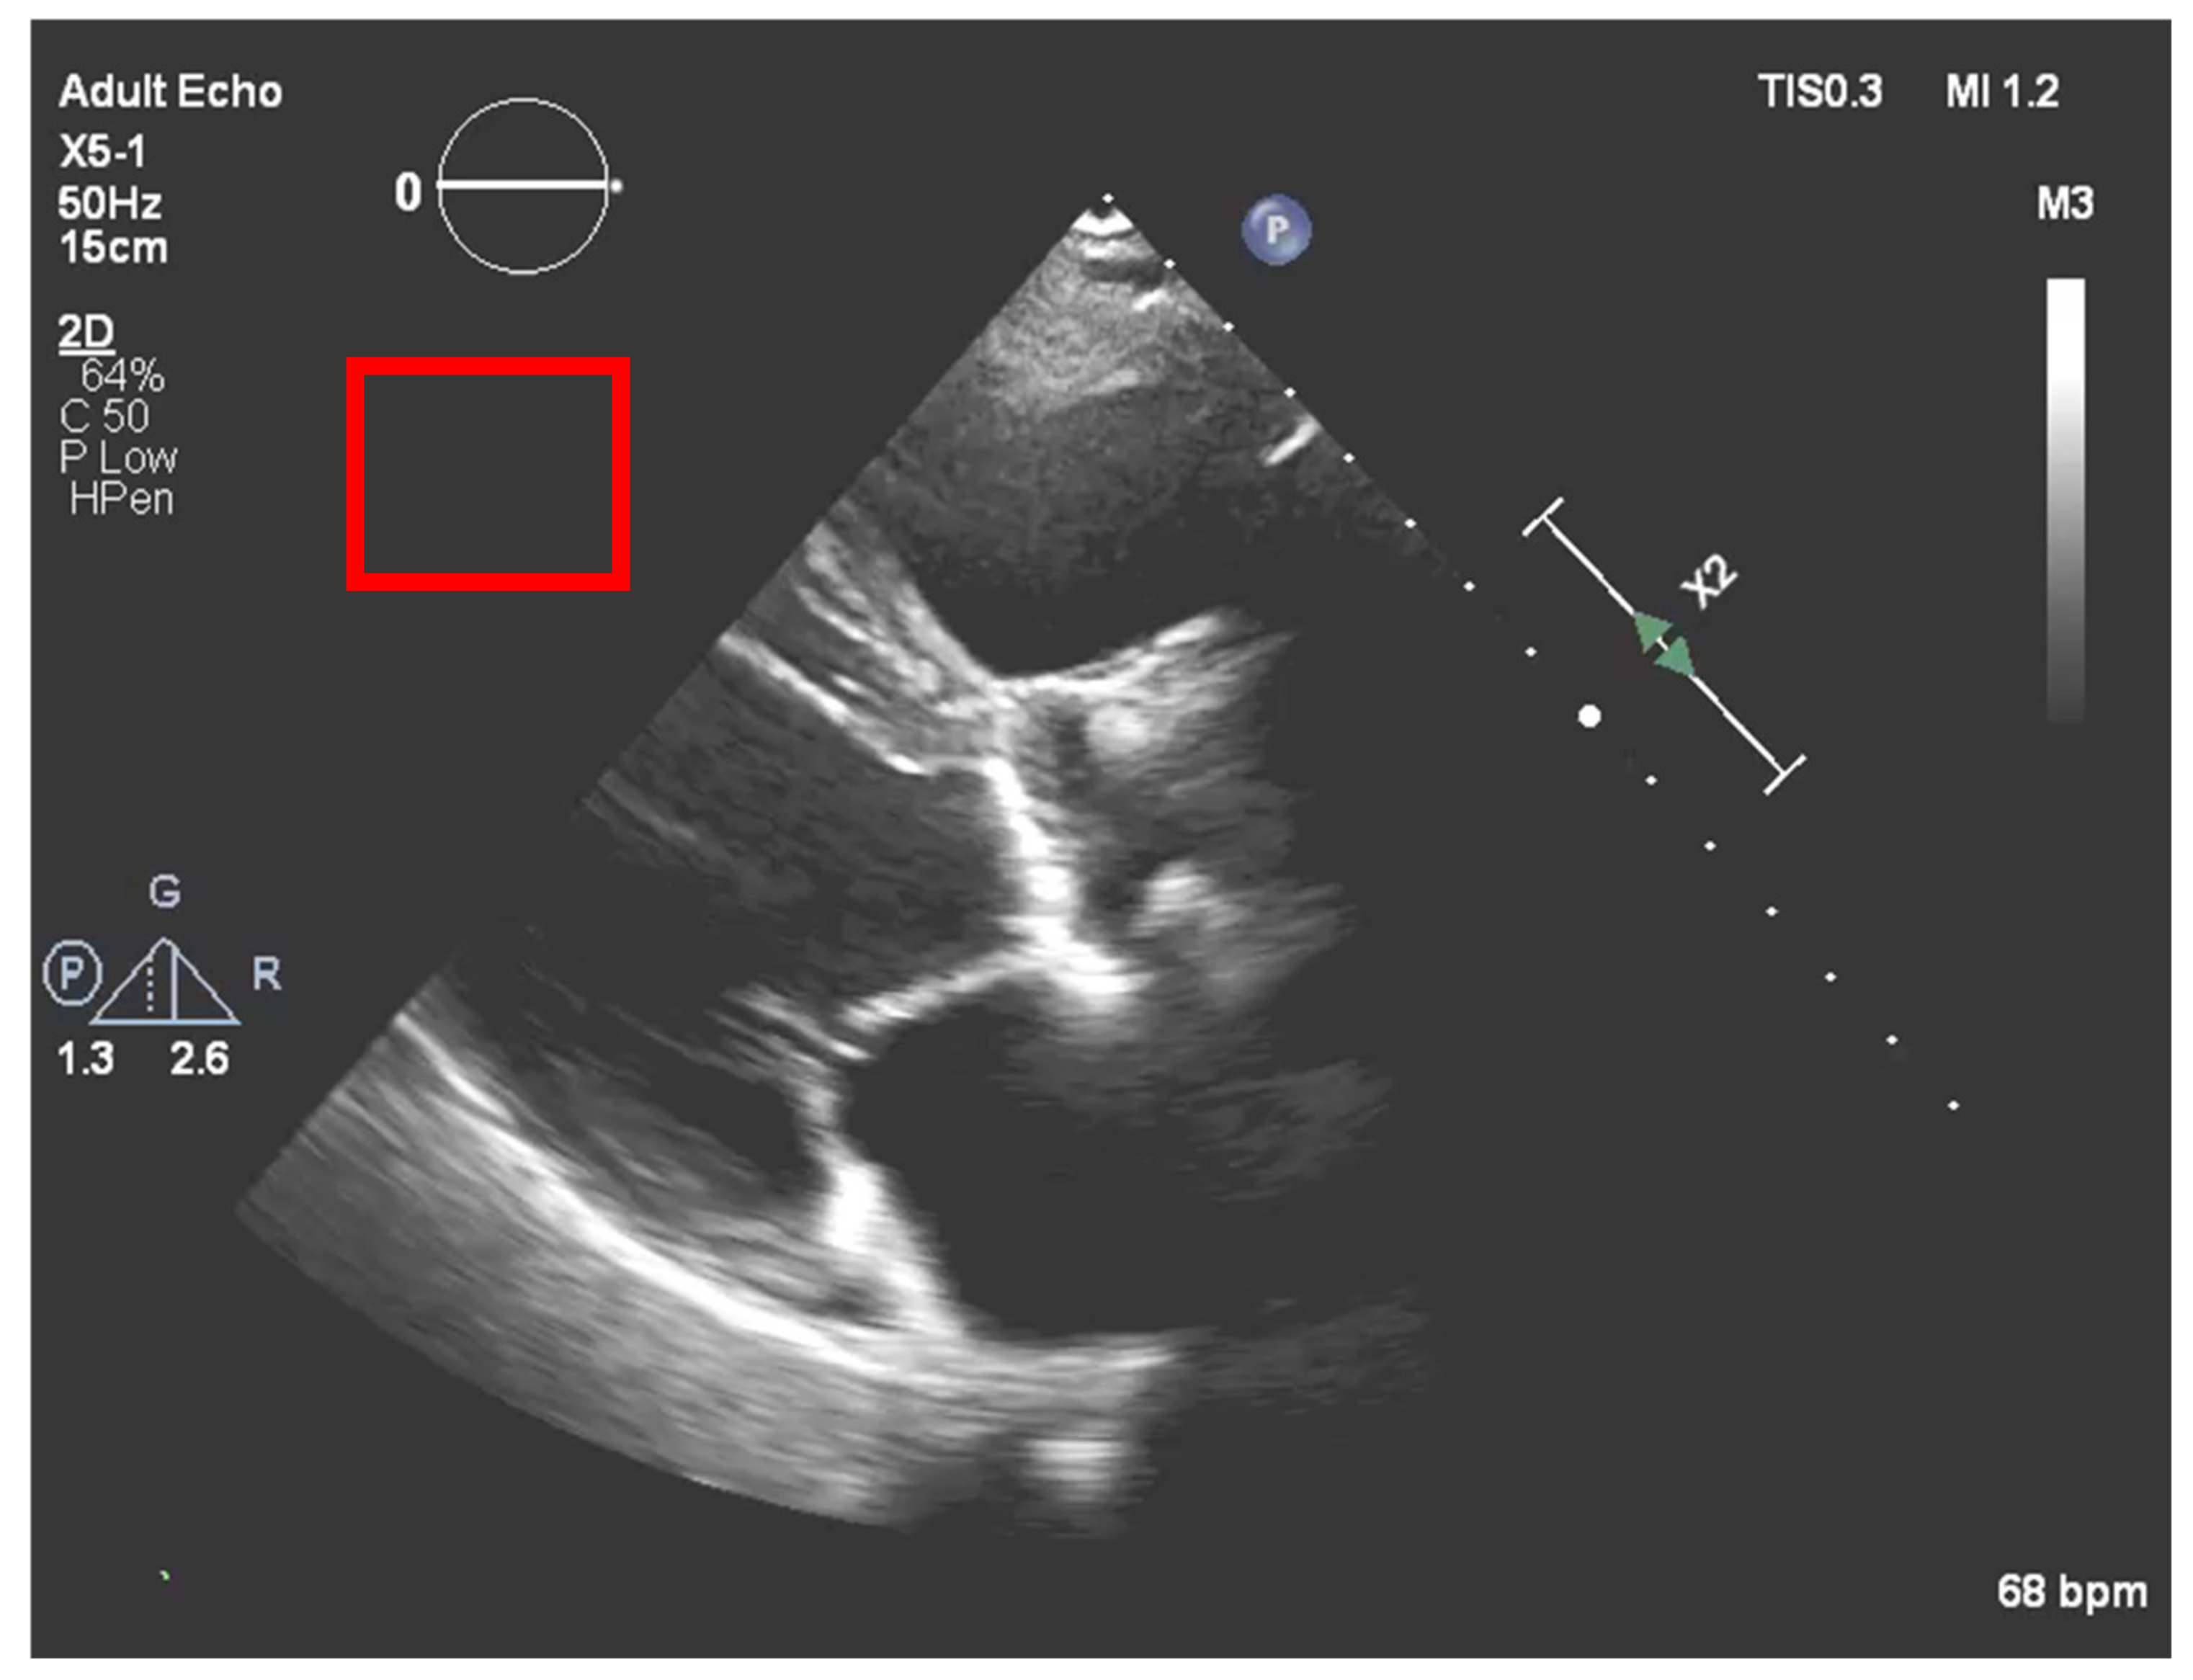

After the echocardiography raw data acquisition, gains are added to the image in a post-processing procedure. In our process, it is necessary to compensate for the new brightness that the image acquires by such a process. To accomplish this, a region outside the ultrasound sector was selected that would act as a normalization boundary of “dark” regions, as represented in Figure 7.

Figure 7. Normalization region of interest (red square) to compensate the post image processing.